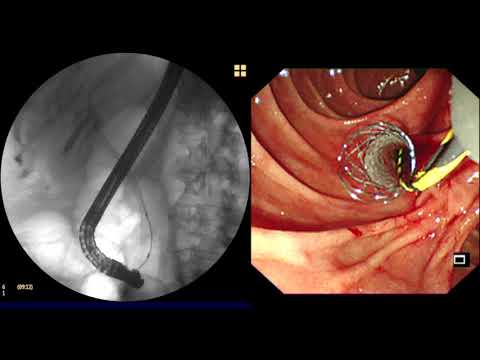

Prótesis Biliares

Es un elemento tubular que da soporte a la vía biliar obstruida permitiendo el paso de la bilis al duodeno.

Las prótesis biliares colocadas por vía endoscópica son una de las alternativas en el manejo paliativo de las neoplasias que obstruyen la vía biliar. Las endoprótesis biliares colocadas por vía endoscópica también han mostrado que mejoran la calidad de vida del paciente.

Las endoprótesis utilizadas para el drenaje endoscópico de la vía biliar son de dos tipos: las plásticas, que han sido las más extensamente estudiadas, y las metálicas